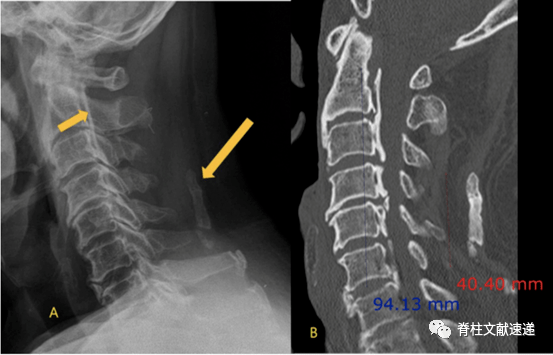

颈椎后纵韧带骨化症opllx线诊断